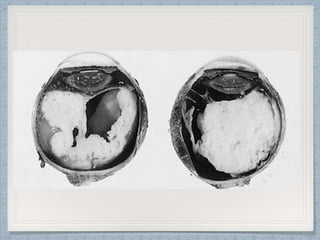

Gross Findings

Of Retinoblastoma

Gross:May be flat and diffuse or elevated, and

may show multicentric foci of origin, especially

in the hereditary type.

Three patterns of growth are recognised :

1Endophytic:growth occurs

inwards into the vitreous.

Cell clusters may detach and

float in the vitreous

(vitreous seeding)

2Exophytic

Growth occurs outwards

Grow between the retina and the pigment epithelium

Associated with non-rhegmatogeneous retinal detachm

3 Diffuse infiltrating growth